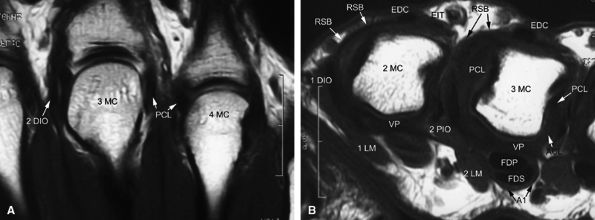

FIGURE 11.2 ● Metacarpophalangeal joints. (A) T1-weighted coronal image. (B) T1-weighted axial image. The proper collateral ligament (PCL) is lax in extension and shows heterogeneous signal intensity on coronal and axial images. ACL, accessory collateral ligament; VP, volar plate; LM, lumbrical; DIO, dorsal interosseous; PIO, palmar interosseous; MC, metacarpal; RSB, radial sagittal band; EDC, extensor digitorum communis; EIT, extensor indicis proprius tendon; FDS, flexor digitorum superficialis tendon; FDP, flexor digitorum profundus tendon; A1, A1 annular pulley.

|